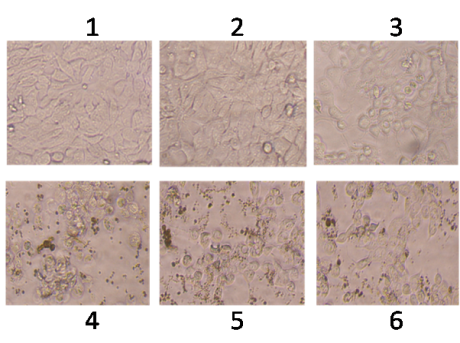

The growth of cancer cells was inhibited in a dose-dependent manner after exposure to the phytochemical (fig. 1, 2), whereas normal human lymphocytes were not affected after exposure (fig. 3). The effect of flavonoid kaempferol on the proliferation of two cancer cell lines (HCT-15 and MDA MB 231) and normal lymphocytes were determined using MTT assay. The IC50 values for kaempferol on HCT-15 and MDA MB 231 were evaluated as 120±3.2 µg/ml and 64±1.2 µg/ml respectively (table 1). When the activity of kaempferol against cancer cells was compared with that against normal lymphocytes it was evident that kaempferol had specific anti-proliferative activity against the two cancer cell lines tested (fig. 4). Further studies were performed based on the IC50 concentrations.

Fig. 1: Effect of phytochemical (kaempferol) on HCT-15, cells treated with concentrations. (1) Control; (2) 10 µg/ml; (3) 25 µg/ml; (4) 50 µg/ml: (5) 100 µg/ml and (6) 150 µg/ml. Cells were visualized under phase contrast inverted microscope (Magnification X40)